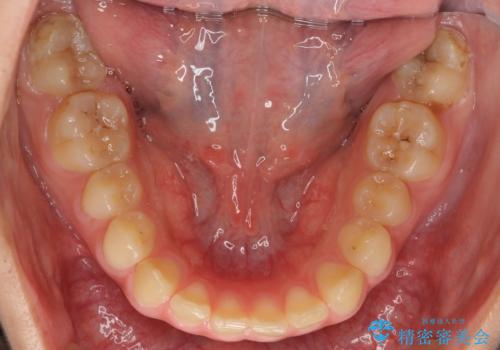

奥歯のかみ合わせが、歯と歯が向かい合わせになっておりまた、歯ぎしりも多い方で装置の脱離も頻繁にありました。

ご自身でしっかり装着しなければならないですが、非抜歯で上顎を遠心移動するのであれば、マウスピース矯正も有用な症例だと思います。ただし、右側の2級関係が厳しいため、遠心移動量がかなり大きくなりそうです。どう治すにしても時間がかかりそうな症状です。